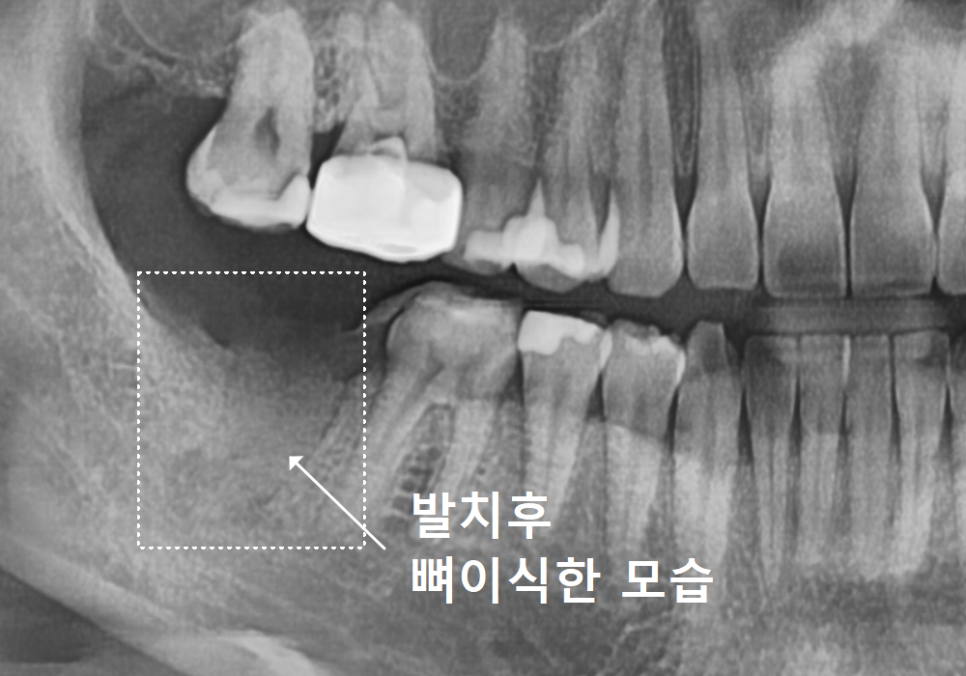

[사례 1] 뼈가 녹아 기다림이 필요했던

지연식립 케이스

강동구 임플란트 기간, 사람마다 왜 다를까? 즉시식립과 지연식립의 결정적 차이

먼저 지연식립을 진행했던

환자분의 사진을 함께 살펴볼까요?

오른쪽 아래 맨 끝 어금니(#47) 부위를 보시면

뿌리 끝부분이 까맣게 보이죠.

뿌리끝에 염증이 생겨서 이 염증으로 인해

뼈가 녹아 까맣게 보이는데요~

잇몸뼈는 밀도가 높을수록

하얗게 나타나고,

염증으로 인해 뼈가 녹아

밀도가 낮아지면 이렇게 까맣게 보이게 됩니다.

염증을 제거하고 뼈이식을 진행한 뒤,

뼈가 튼튼하게 굳기를 2개월 정도 기다렸습니다.